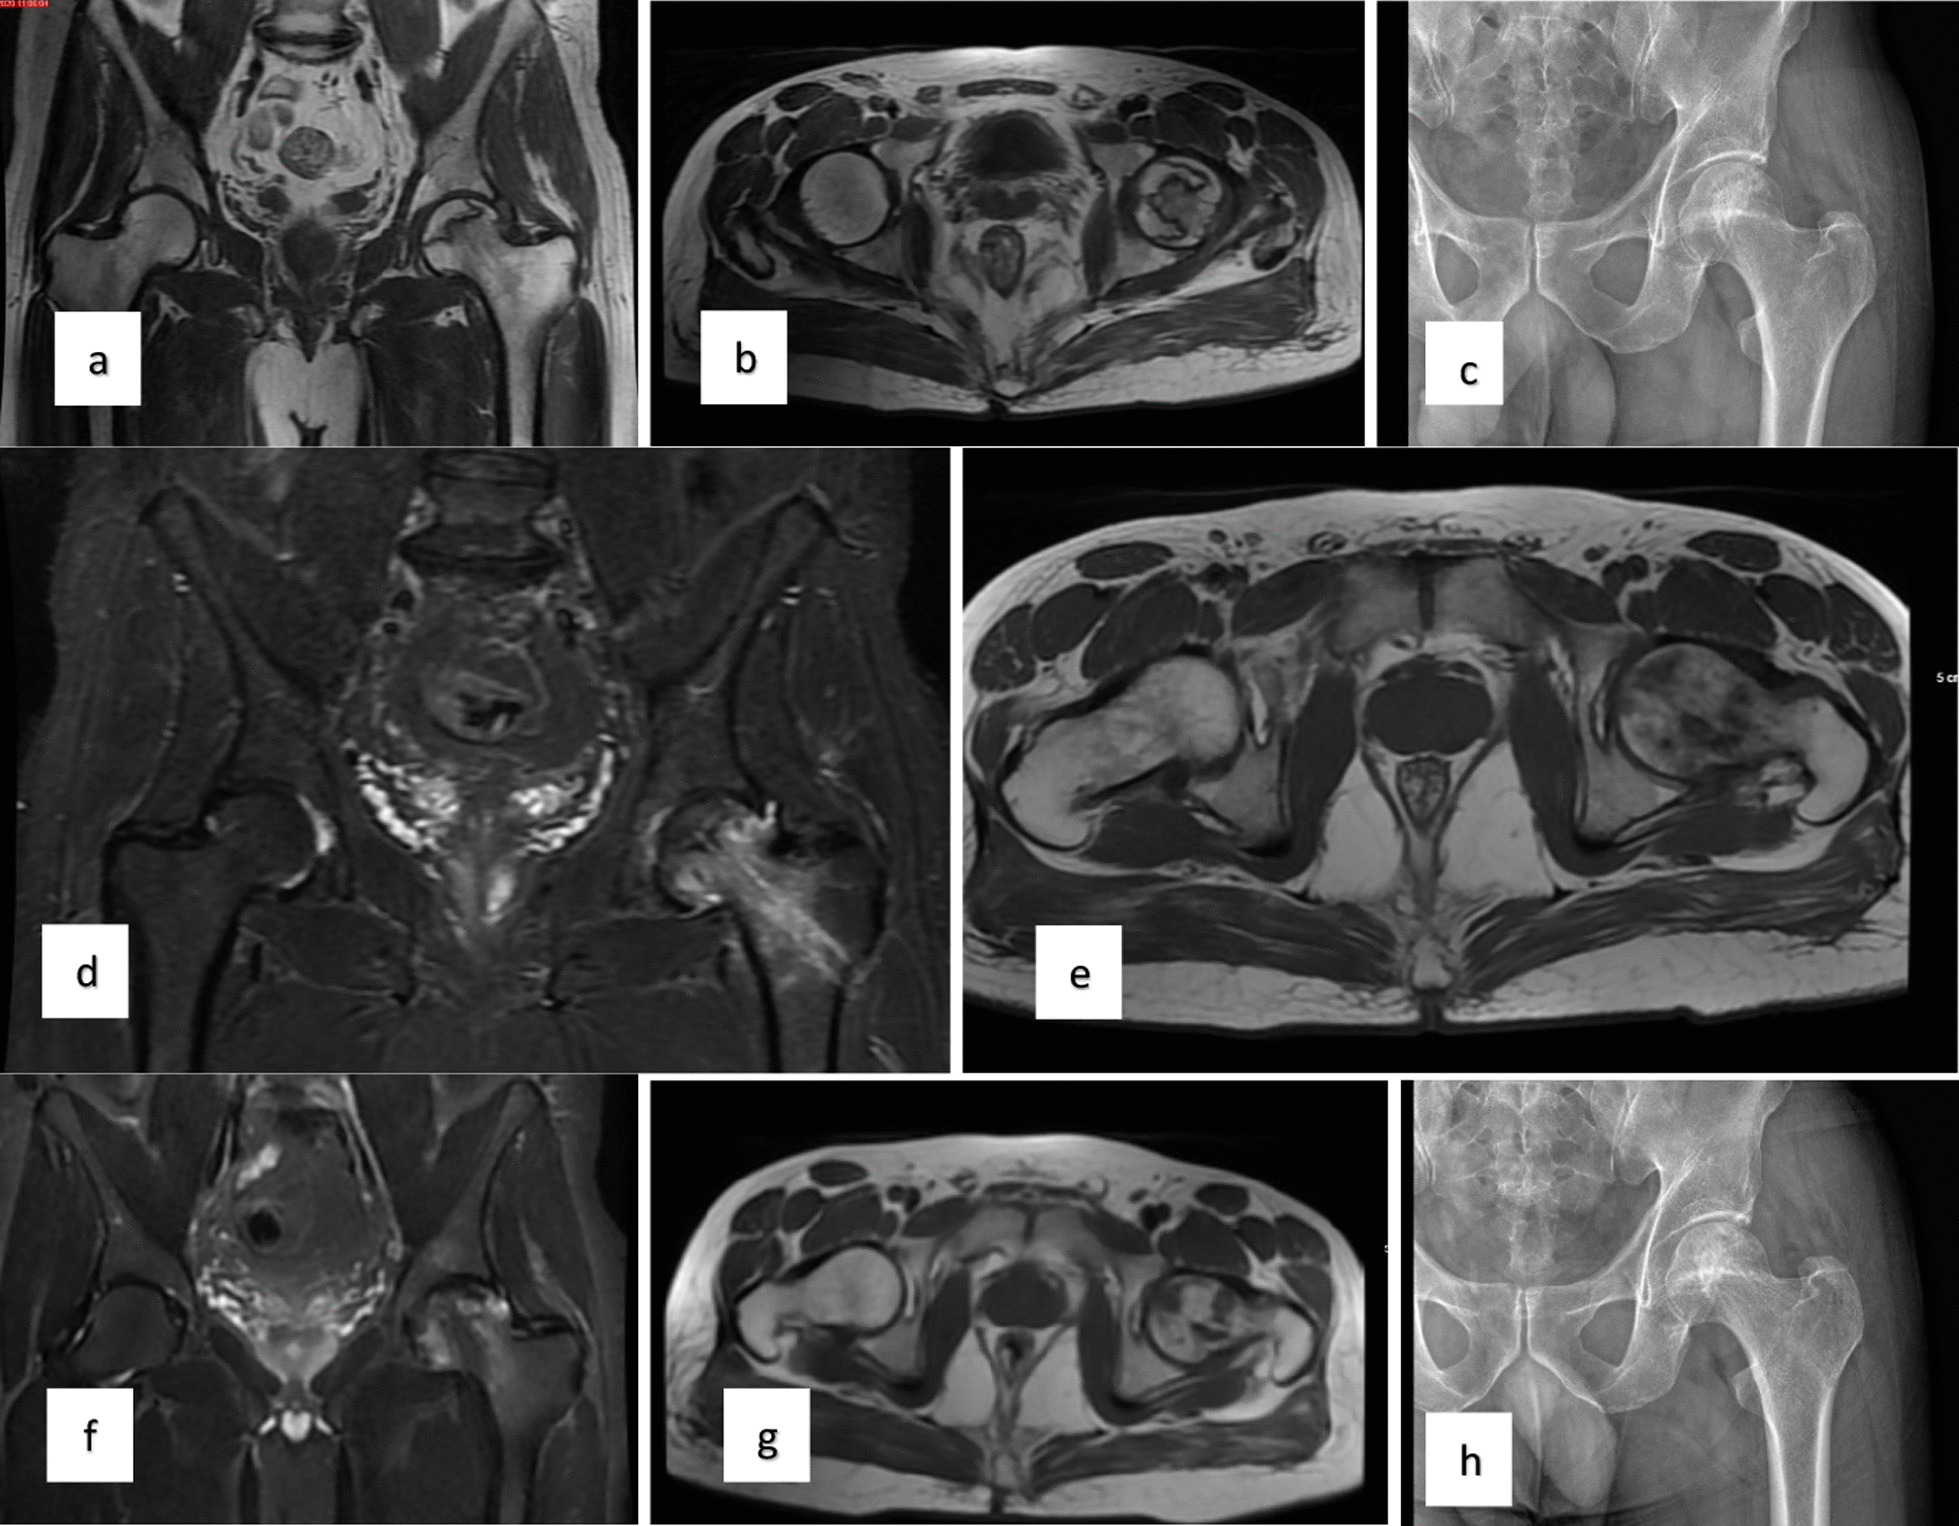

對患者的術(shù)前、3個(gè)月、6個(gè)月、1年和2年隨訪進(jìn)行評估(圖1)。

當(dāng)評估第1組和第2組的VAS評分時(shí),得出結(jié)論:基線和第3個(gè)月的VAS評分相似;6、12、24個(gè)月時(shí)差異有統(tǒng)計(jì)學(xué)意義,第2組VAS評分明顯較低。比較各組患者的HHS時(shí)得出的結(jié)論是,基線評分相似,第2組在第24個(gè)月時(shí)有顯著改善。此外,兩組治療前后的HHS均顯著改善。第1組和第2組患者VAS評分變化見表1,HHS評分見表2(圖2)。